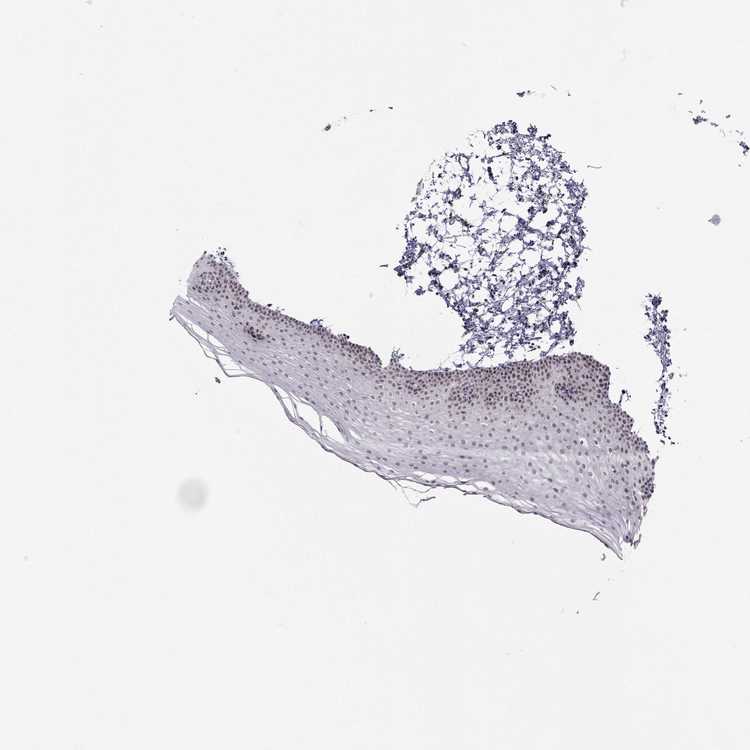

TISSUE PRIMARY DATA ORAL MUCOSA Show tissue menu

ORAL MUCOSA - Antibody stainingi

Antibody staining in the annotated cell types in the current human tissue is reported as not detected, low, medium, or high, based on conventional immunohistochemistry profiling in selected tissues. This score is based on the combination of the staining intensity and fraction of stained cells.

Each image is clickable and will lead to virtual microscopy that enables deeper exploration of all samples and also displays staining intensity scores, fraction scores and subcellular localization as well as patient and tissue information for each sample.

Antibody HPA061693

Squamous epithelial cells Low